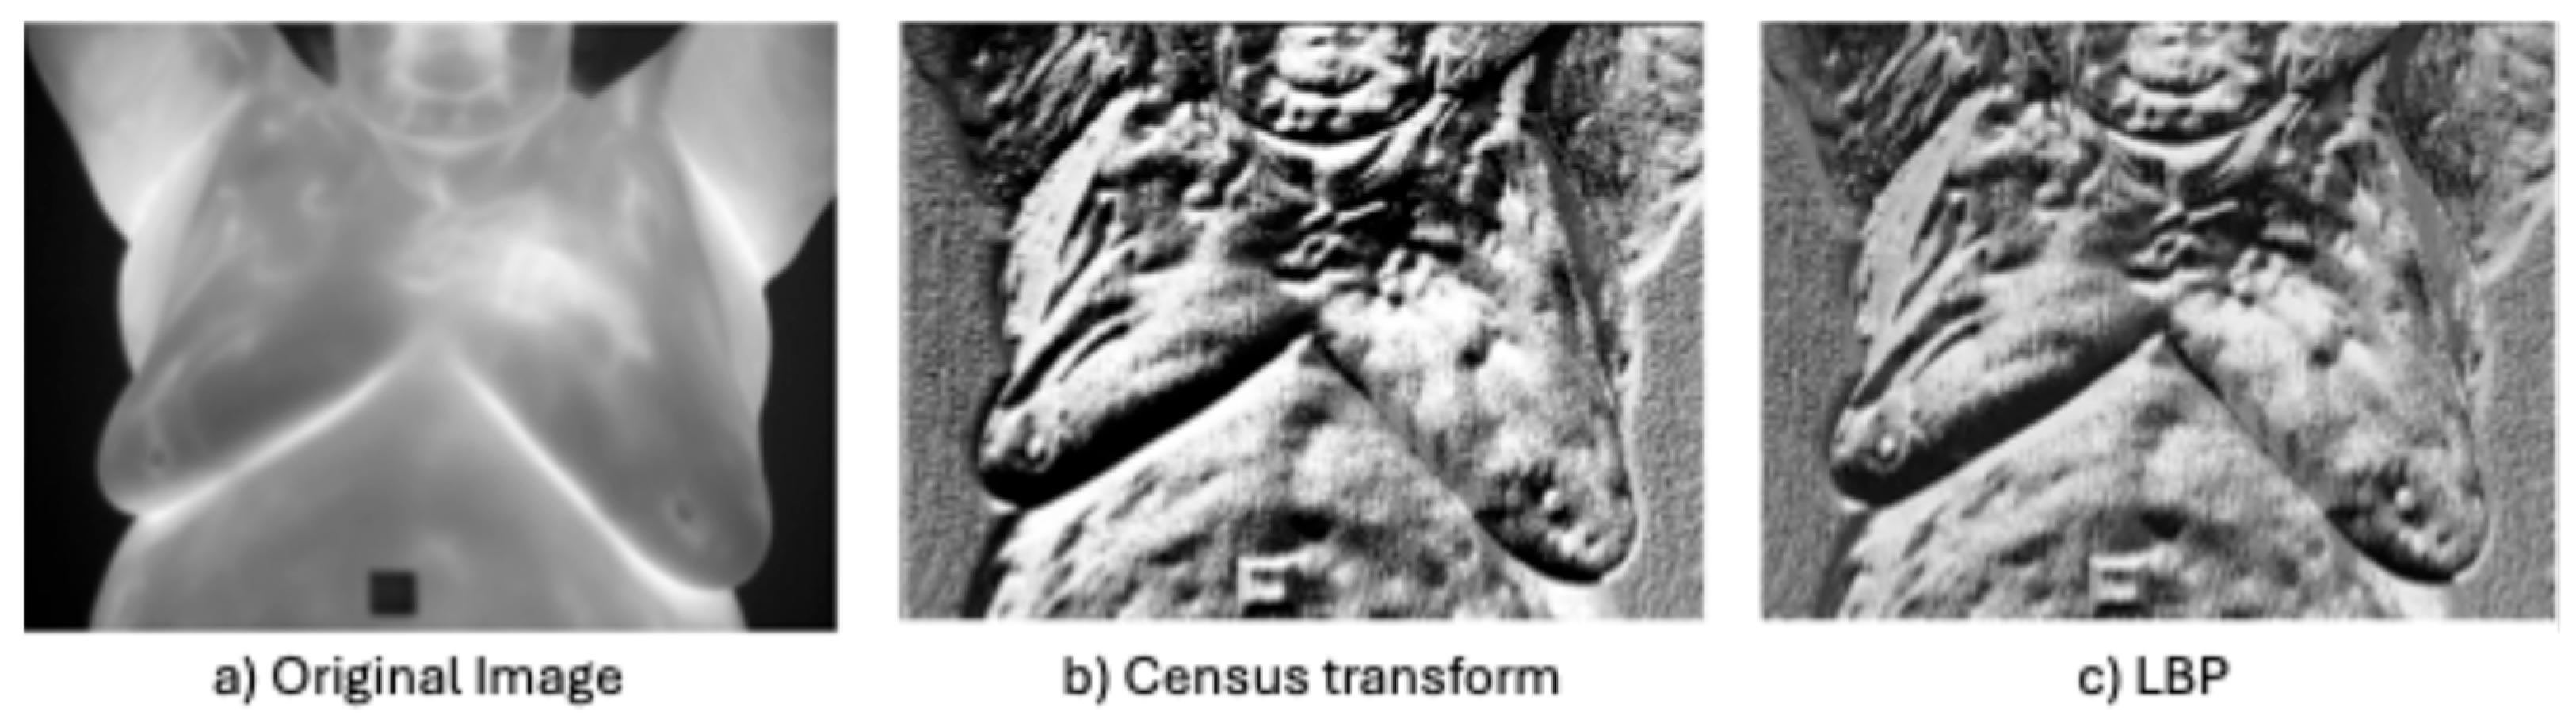

- Non-parametric local transforms: rely on the relative ordering of local pixels, not on their intensity value. It includes Census Transform (CT) [86], Local Ternary Pattern (LTP) [76], Local Directional Number Pattern (LDN) [89], and local binary pattern (LBP) [87], which encode the local textural and structural properties of an image as binary codes.